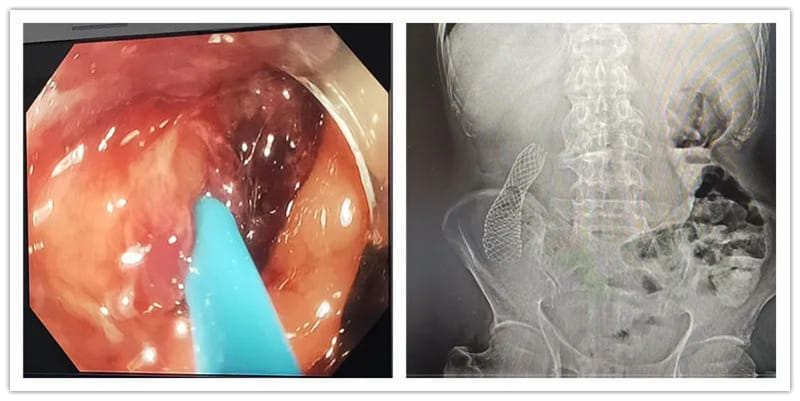

病例二:老年患者韦某某,因“排便困难数月,加重一周”就诊于消化内科,入院时患者腹痛、腹胀明显,完善相关检查后,CT提示:肝内多发转移灶,行电子结肠镜检查,于结肠肝曲部发现了原发肿瘤病灶。在做好充分术前准备后,消化内科贺黔黔医生为其实施了内镜下结肠支架置入术。术后,患者即排出大量宿便,腹痛、腹胀已明显好转,极大减轻了患者痛苦。

结肠癌支架置入前(左)及置入后(右)